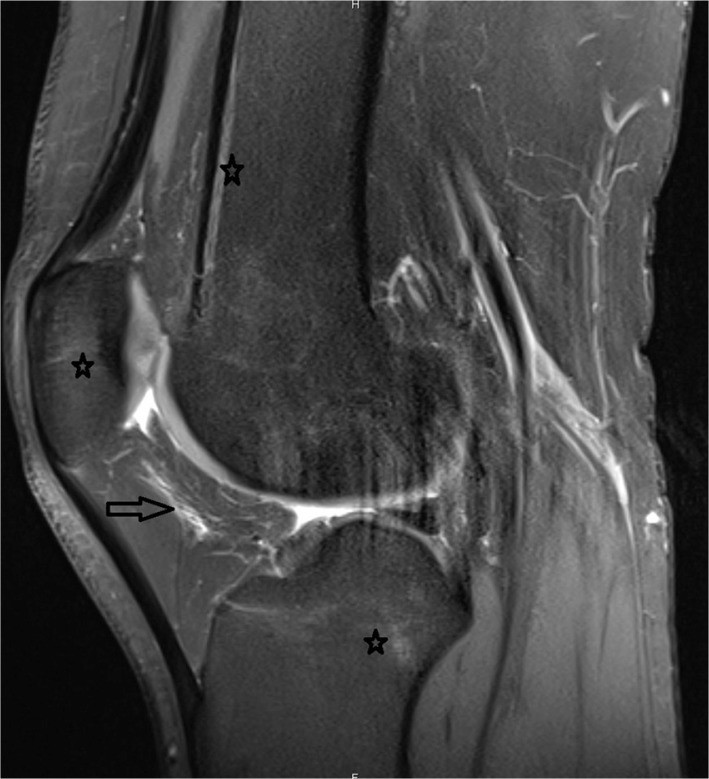

Приклад: знімок коліна 27-річної жінки без симптомів, що займається кенгу-джампінгом. Проксимальна зірочка показує поздовжній набряк кісткового мозку (BME) стегна, середня зірочка показує BME надколінка, дистальна зірочка показує BME тибіофеморального суглоба. Стрілкою показаний набряк підколінникової жирової тканини. Тендинопатія надколінка та чотириголового м'яза проявляється як зміна сигналу у місці їх прикріплення.

У 32 (88,9%) з 36 колін кенгу-джамперів спостерігалися одна або кілька аномалій — зокрема найчастішою патологією був набряк кісткового мозку, який МРТ виявила у 32 колінних суглобах (88,9%). Також часто зустрічалася тендинопатія чотириголового м'яза (80,6%), тендинопатія надколінка (63,9%), тендинопатія литкового м'яза (63,9%), набряк інфрапателярної жирової тканини (75%), набряк супрапателярної жирової тканини (63,9%), зміна сигналу меніска (72,2%) та пошкодження хрящів у пателофеморальному суглобі (72,2%).